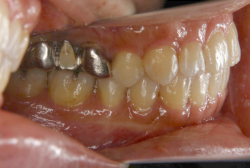

「左奥歯でものが噛めない」という主訴で来院したケースです。診断の結果、基本的には「叢生」という隙間が足りないと言うことが原因の凸凹症例でしたが、左下の乳歯が高校生になってもまだ残存している状態で、そのせいで噛み合わせが極端に悪くなっていました。

検査の結果、乳歯の下には後継ぎの永久歯が先天的に欠如していました。配列の凸凹が厳しく非抜歯で矯正することは難しく、仮に無理をして非抜歯治療をしても後々「後戻り」が懸念されることから、このような症例の場合は通常、上下顎左右第一小臼歯を抜歯させていただくのですが、左下は乳歯を抜歯して、第一小臼歯は残すことにしました。これで結果として、小臼歯部を上下左右で一つずつ減らしたのと同じ状況になります。治療後は歯並びが綺麗になっただけでなく、噛み合わせ的にも正しい状態が確立しています。

このように、先天的に永久歯が足りないという症例は最近増えています。親知らずはなくても特に問題になりませんが、その他の歯が足りないと言うのは審美的にも機能的にも重大な障害となります。しかし、矯正治療を正しく行えば、結果として歯がすべてあった場合と全く同じ仕上げにすることも可能です。